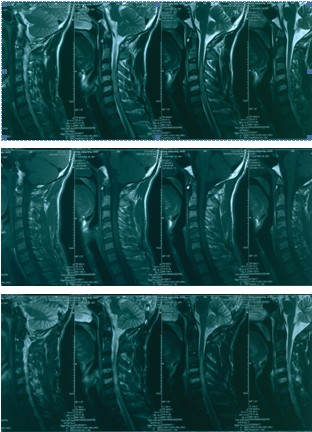

2012-11-18 车祸致四肢感觉、运动及二便功能障碍。

查体:意识清楚,呼吸均匀,查体合作。双侧感觉平面颈4,运动平面颈5. 颈6以下轻触觉保留至肛周,针刺觉消失。颈5以下只有肛门括约肌保留运动功能。下肢肌张力0级。腱反射消失。球海绵体反射可引出。当地医院行X片、CT、MRI检查